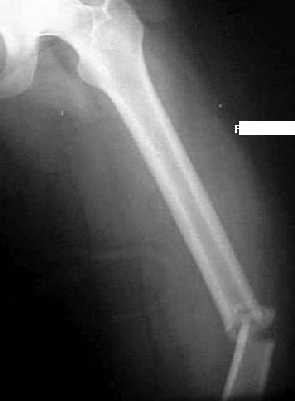

Un paciente varón de 73 años ingresa en Urgencias inconsciente, después de un accidente de tráfico, con fracturas de 3ª,4ª,5ª y 6ª costillas derechas y fractura diafisaria de femur izquierdo.

Escenario 7:Decisiones Quirúrgicas (Traumatologia):Paciente con fractura intertrocantérica femur.Mejor método de osteosíntesis

Escenario 7:Decisiones Quirúrgicas (Traumatologia)